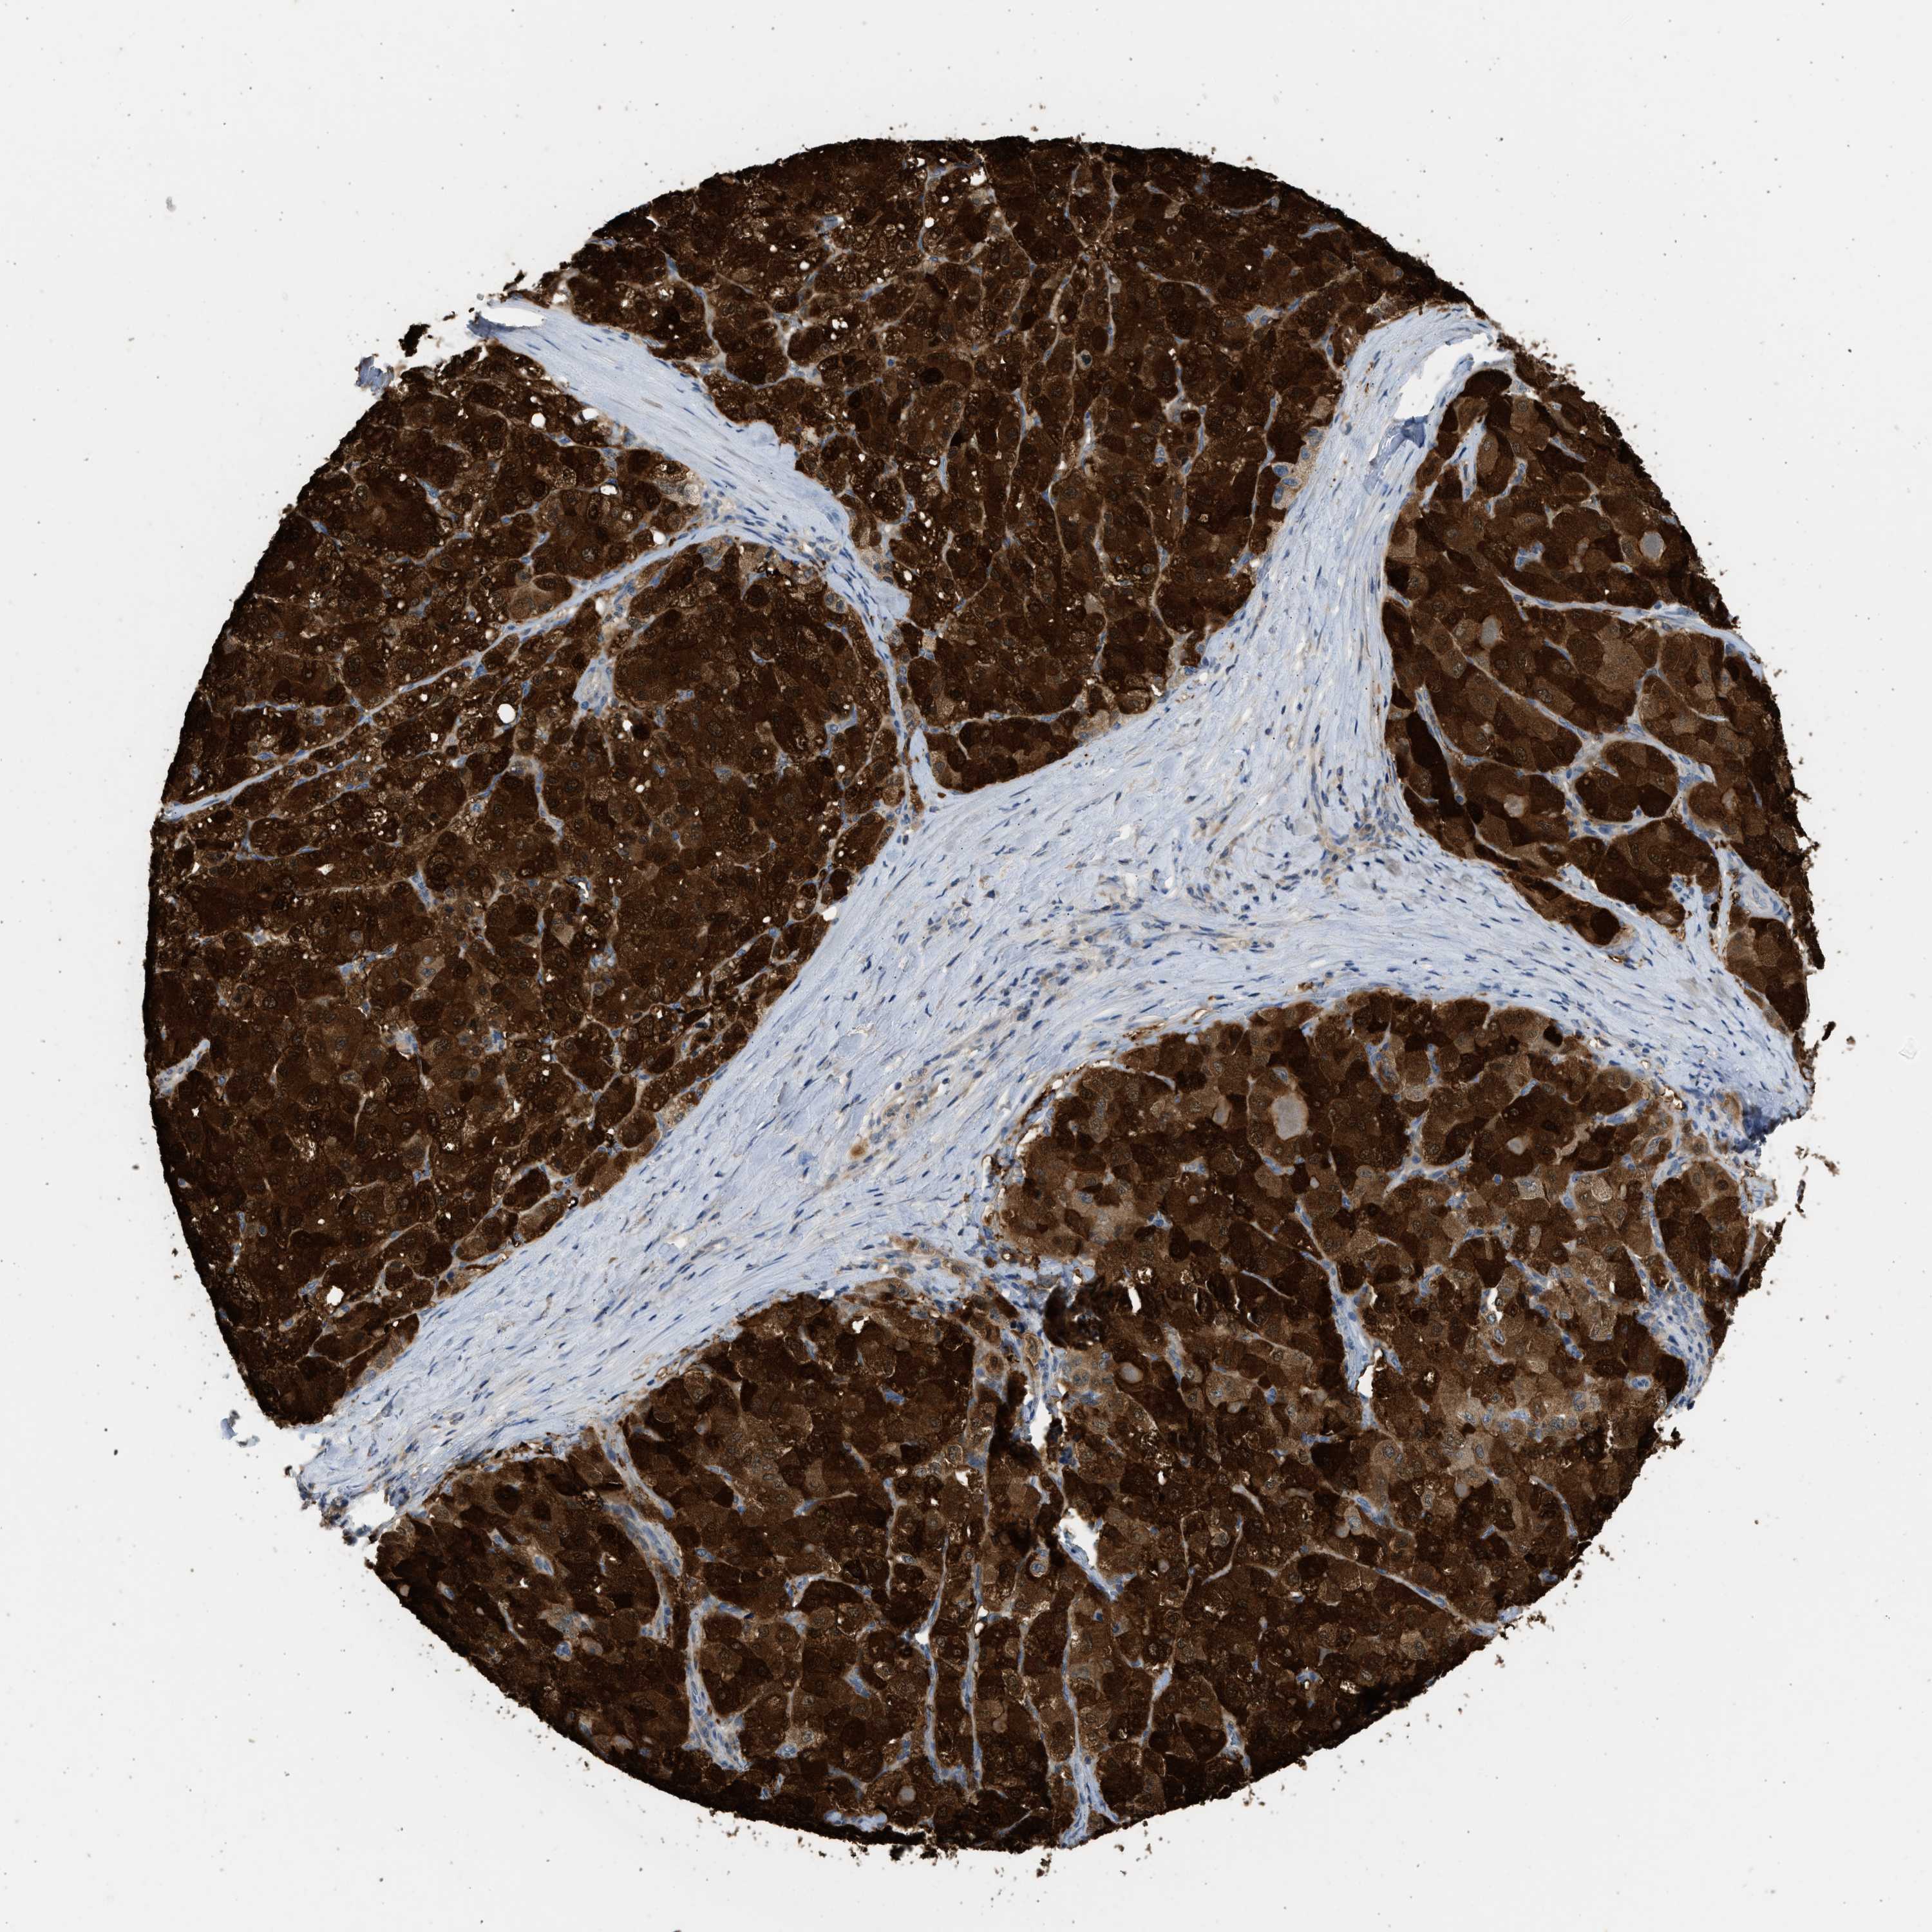

LIVER CANCER - Protein expressioni

A mouse-over function shows sample information and annotation data. Click on an image to view it in a full screen mode. Samples can be filtered based on level of antibody staining by selecting one or several of the following categories: high, medium, low and not detected. The assay and annotation is described here.

Note that samples used for immunohistochemistry by the Human Protein Atlas do not correspond to samples in the TCGA dataset.

Antibody stainingi

Antibody staining in the annotated cell types in the current human tissue is reported as not detected, low, medium, or high, based on conventional immunohistochemistry profiling in selected tissues. This score is based on the combination of the staining intensity and fraction of stained cells.

Each image is clickable and will lead to virtual microscopy that enables deeper exploration of all samples and also displays staining intensity scores, fraction scores and subcellular localization as well as patient and tissue information for each sample.

Antibody HPA041487

Antibody HPA063633

Antibody CAB018755

Staining

High

Medium

Low

Not detected

Intensity

Strong

Moderate

Weak

Negative

Quantity

>75%

75%-25%

<25%

None

Location

Nuclear

Cytoplasmic/membranous

Cytoplasmic/membranous,nuclear

Cholangiocarcinoma

Carcinoma, Hepatocellular, NOS